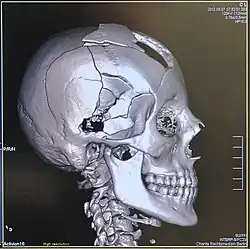

Volume rendering

3D human skull from computed tomography data

A threshold value of radiodensity is set by the operator (e.g., a level that corresponds to bone). With the help of edge detection image processing algorithms a 3D model can be constructed from the initial data and displayed on screen. Various thresholds can be used to get multiple models, each anatomical component such as muscle, bone and cartilage can be differentiated on the basis of different colours given to them. However, this mode of operation cannot show interior structures.[117]

Surface rendering is limited technique as it displays only the surfaces that meet a particular threshold density, and which are towards the viewer. However, In volume rendering, transparency, colours and shading are used which makes it easy to present a volume in a single image. For example, Pelvic bones could be displayed as semi-transparent, so that, even viewing at an oblique angle one part of the image does not hide another.[118]